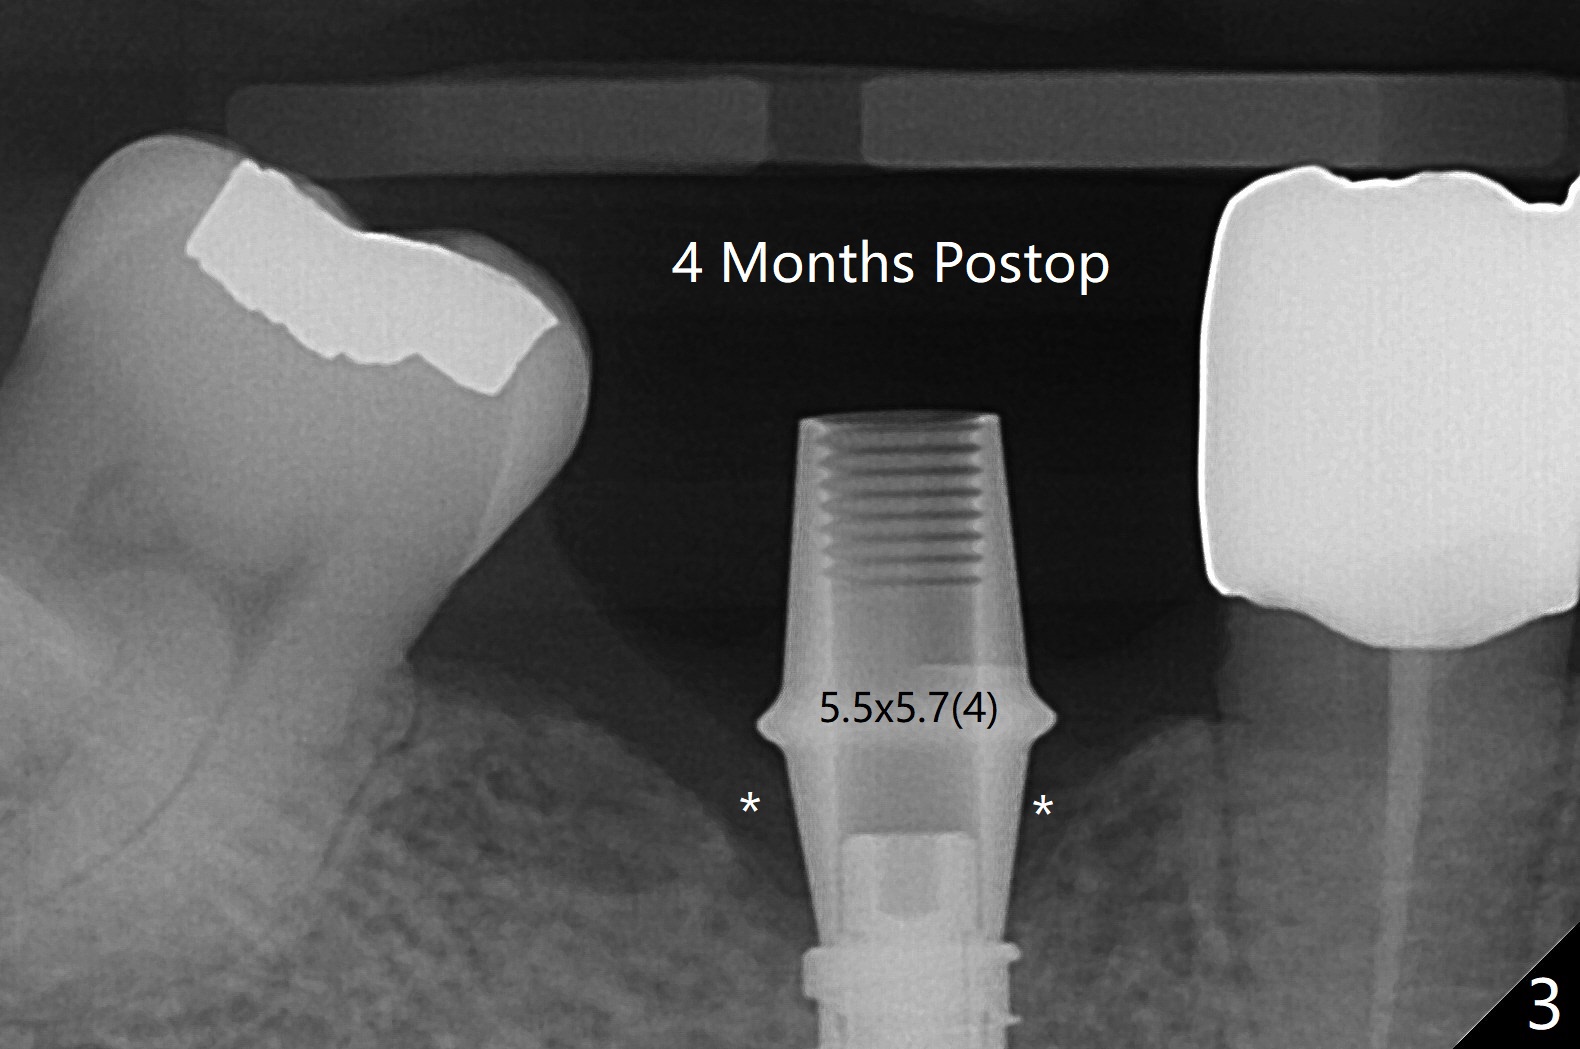

Since the preop ridge looks narrow at #30, incision is made, which makes it easy for observation of osteotomy. First, a 10.5 mm bone trimmer makes a deep dimple with apparently moderate ridge wide enough for a 4 mm implant. The patient has hypertension and cannot lie down for long. The bone density feels not high; a 4x11 mm (instead of 9 mm) implant is placed for 10 mm osteotomy (Fig.1 (~ 35 Ncm)). After use of 6 mm bone profile drill, there is bone buccal (less) and lingual to the implant. A 5.5x4 mm healing abutment is inserted, barely supragingival. As the implant is 1 mm longer than the design, regional panoramic X-ray is taken to determine clearance from the Inferior Alveolar Canal (Fig.2 red dashed line (the upper border). There is crestal bone loss 4 months postop (Fig.3,4). It appears that the implant was placed excessively deep. There is no implant thread exposure 9 months post cementation (Fig.5,6).